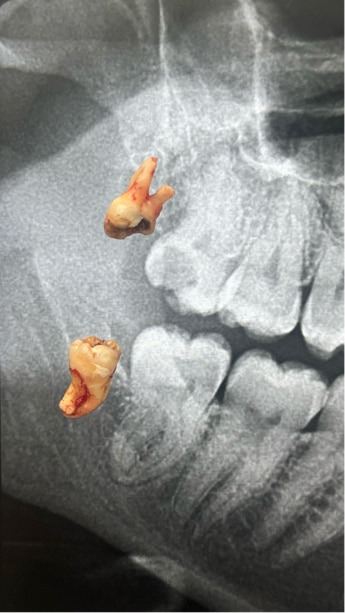

Impaction

Safe removal of teeth stuck inside the jaw by experts conserving the structures around for quick and comfortable healing.